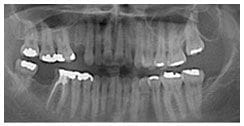

術後X光片